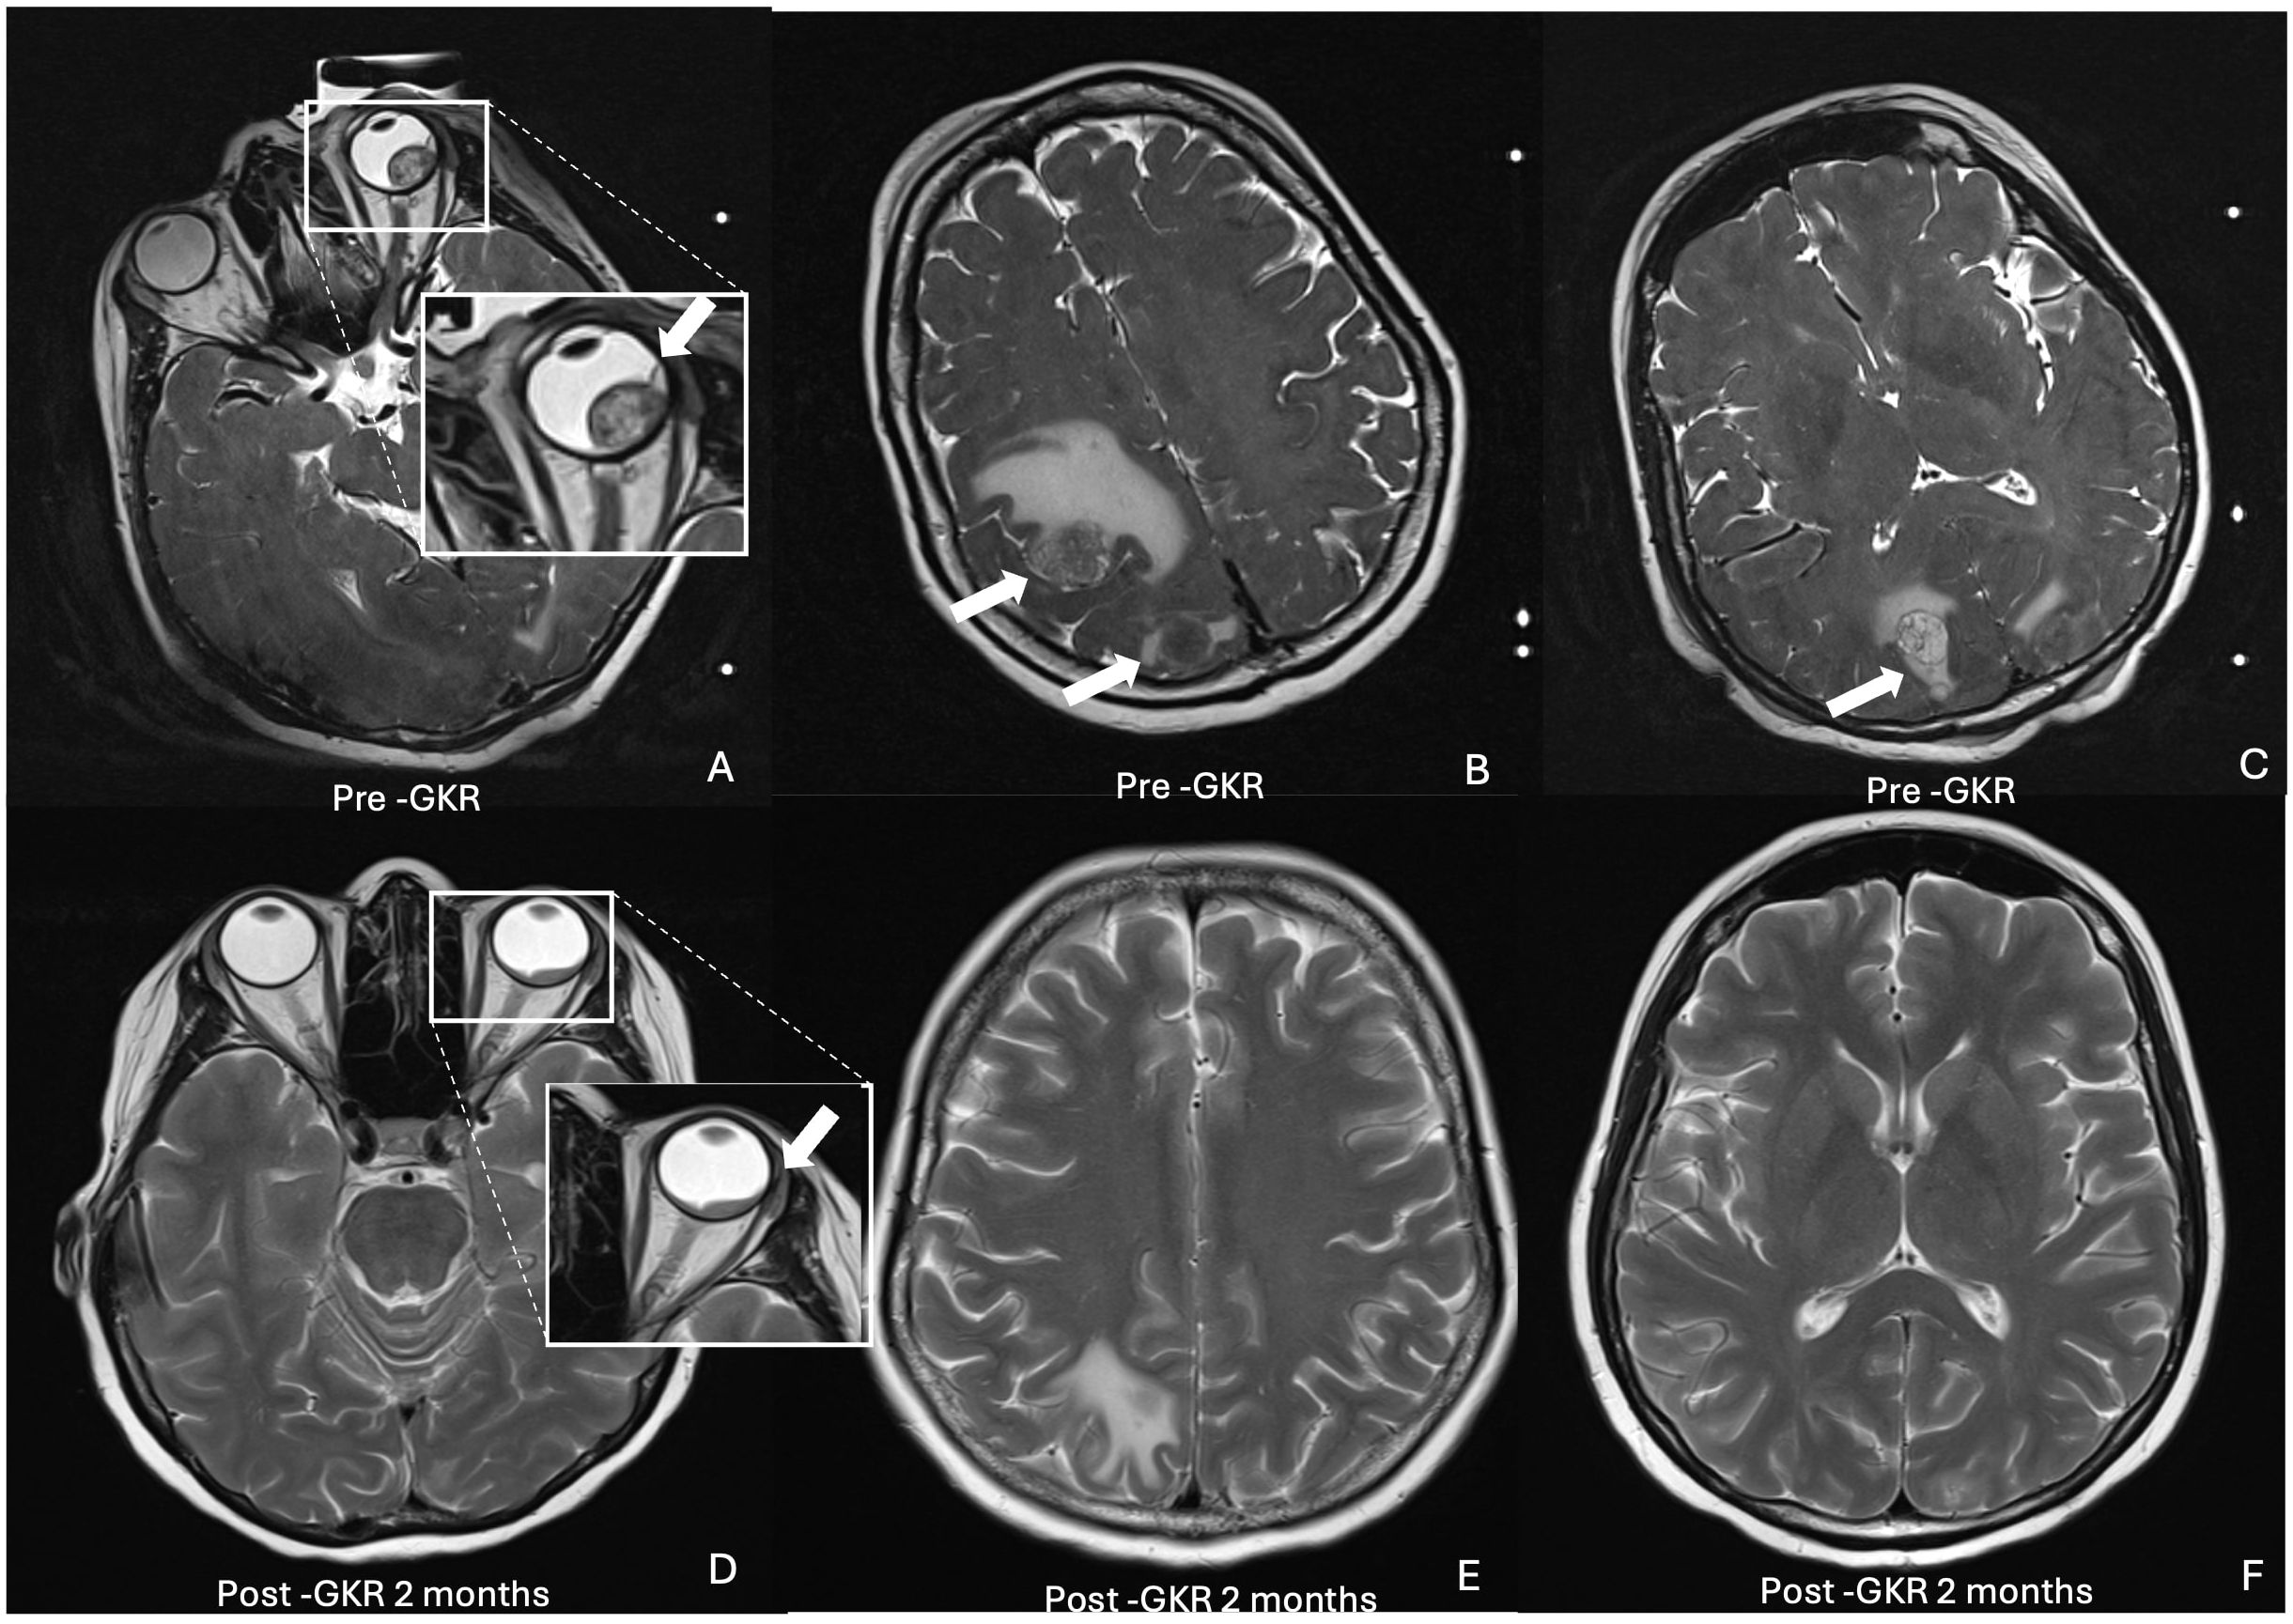

Introduction: Choroidal metastasis generally has poor prognosis and are most commonly originated from breast carcinomas.1,2 While systemic chemotherapy offers therapeutic benefits, local therapies are often necessary for symptom management and tumor control. Gamma Knife Radiosurgery (GKR), originally developed for intracranial lesions, has emerged as a promising treatment for choroidal metastasis, offering high precision and minimized toxicity with fewer ocular side effects compared to conventional radiotherapy. This case report explores the use of GKR in a patient with choroidal and brain metastases from breast carcinoma. Case Presentation: A 44-year-old woman with a history of treated left breast carcinoma presented with 3 months gradual vision loss in her left eye. Her visual acuity at presentation was Counting Fingers (CF). Imaging revealed a choroidal metastasis along with multiple brain metastases. The patient underwent GKR for both choroidal and intracranial metastases, receiving doses ranging from 16-18 Gy at 50-90% isodose. Following treatment, significant tumor regression was observed, with marked reduction in retinal detachment and vision improvement to 6/18. At post-GKR 6 months, both the choroidal mass and retinal detachment had fully resolved, but her visual acuity remained limited due to fovea atrophy. Conclusion: This case demonstrates GKR's potential as a non-invasive and effective modality for simultaneous treatment of choroidal and intracranial metastases. In palliative settings, especially for patients with limited life expectancy, GKR can provide symptomatic relief and improved life quality with minimal invasiveness, which is particularly valuable for younger patients facing advanced metastatic cancer. The importance of a multidisciplinary approach in managing complex metastatic disease is also highlighted. Future studies are warranted to fully define the role of GKR in choroidal metastasis and its long-term sequelae.